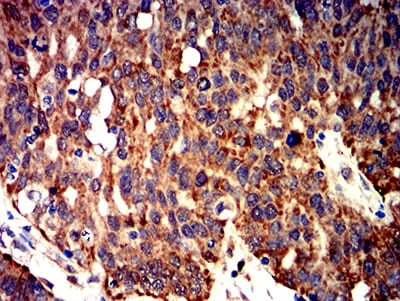

- Immunohistochemical analysis of paraffin-embedded human ovarian cancer tissues using BCL2L2 mouse mAb with DAB staining.